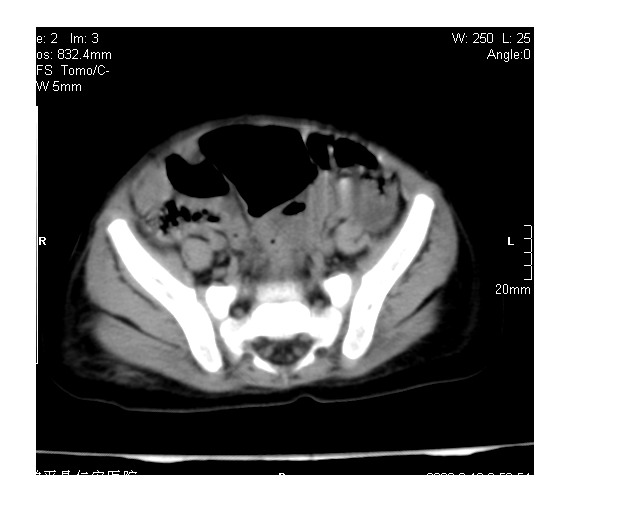

以下是引用lkc8963在2008-3-16 12:49:00的发言:[br]盆底巨大混杂密度肿块,富含多种组织成分包括脂肪/液体/软组织/钙化,边界清楚,向前压迫肠管及膀胱,向后突入骶尾部皮下脂肪层,首先考虑畸胎瘤,诊断时需要与脊柱裂/囊性淋巴管瘤等区别。